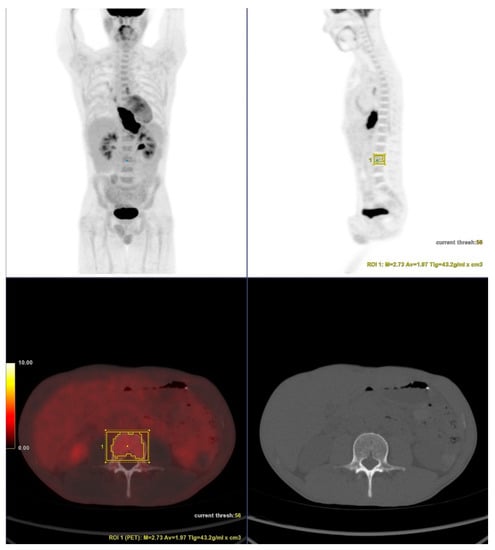

Volumes of interest (VOIs) were drawn over in one of the L3-L5 vertebral bodies, preferably L3 (Figure 1). Care was taken to exclude bones with fractures. Automatic isocontour (set at 75% of the maximum SUV) was generated, and the mean SUV was calculated.

Figure 1.

18F-FDG PET/CT showing a patient with esophageal cancer. Volumes of interest (VOIs) were drawn over in one of the L3-L5 vertebral bodies, preferably L3. Care was taken to exclude bones with fractures, as shown in CT slice. Automatic isocontour was generated, and the mean SUV was calculated.